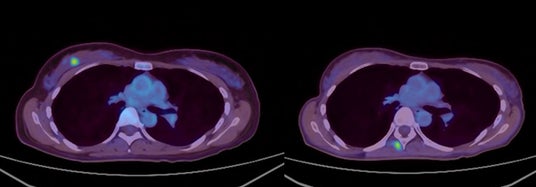

・FDG-PET陽性の浅在性腫瘍に対するBNCT(jRCTs031240204)治療10例目:初発乳がん(未手術)

FDG-PETにおける集積がSUV5からSUV1へ低下。治療1カ月後の時点で触診上腫瘍が確認できなくなり、その後2~4カ月の画像診断においても腫瘍は確認されませんでした。(効果判定はCR)

(MRI画像) 左:照射前 右:照射後4か月